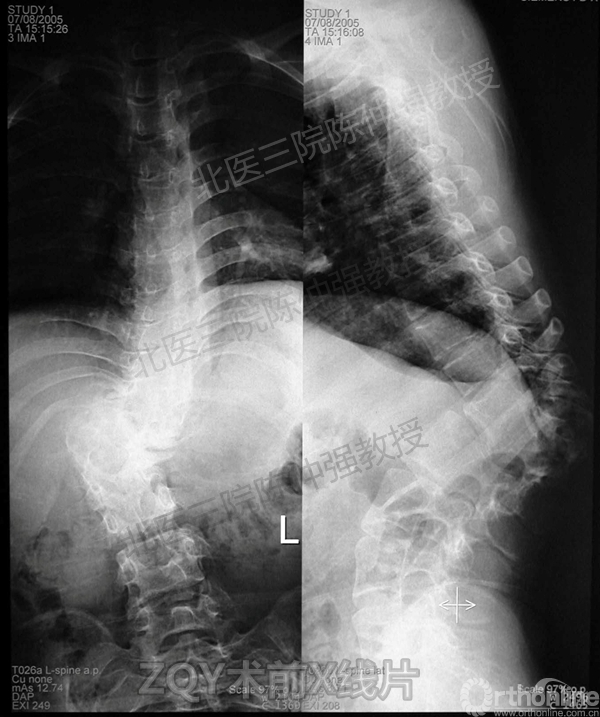

2005年,陈仲强教授在AOSpine年会上分享了一例胸腰椎陈旧结核性侧后凸畸形病例。资料如下:

ZQY术前

患者女性17岁,胸腰椎陈旧结核性侧后凸畸形,局部呈“麻花状”扭转,无神经功能受损表现。2005年,陈仲强教授带领团队实施后路+侧前方联合入路脊柱节段切除、双轴旋转矫形术。术后患者外观显著改善,神经功能正常。术后随访证实患者截骨矫形节段骨性融合良好,矫形效果持续良好。